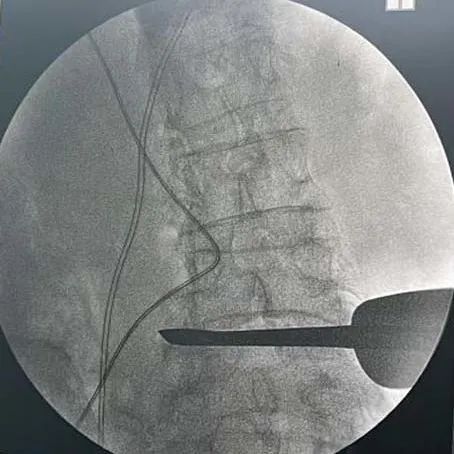

透視確認(ren)手術節段(duan)——

通道(dao)建(jian)立及椎(zhui)間減(jian)壓——

植入(ru)融合器,透視確認融合器位(wei)置——

透(tou)視確認固(gu)定夾——

插片融合器植入前后影像對(dui)比——

椎間隙高度撐開效(xiao)果顯著,椎(zhui)間孔空(kong)間恢復明顯